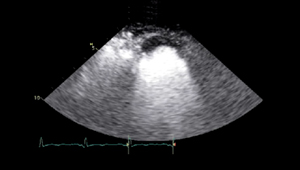

- 첨단 CT와 MRI, 그리고 심초음파 등 최정밀 영상을 이용한 심장진단을 통합적으로 이용할 수 있습니다.